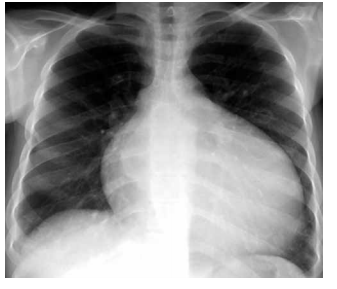

Paciente do sexo masculino, 43 anos de idade, sem

doenças prévias, apresenta dispneia há cerca de 1 ano,

inicialmente aos grandes esforços, evoluindo progressivamente para moderados e pequenos esforços. Nega

tosse, febre, dor torácica, tabagismo, uso de álcool ou de

drogas ilícitas. Exame físico: PA: 112 x 88 mmHg, pulso:

112 bpm e frequência respiratória: 16 ipm; ausculta pulmonar com crepitações em 1/2 de ambos os pulmões.

A radiografia realizada é mostrada a seguir.